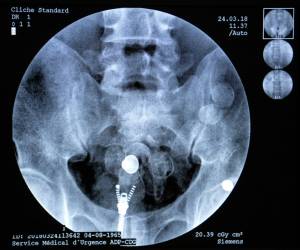

AFP/File / Christophe ARCHAMBAULT Long gone are the days of swallowing cocaine stuffed into condoms and closed up with scotch tape -- today's smugglers have gone high-tech. The Guyana pods are all the same: small, black, heat-sealed capsules about three centimetres (1.2 inches) wide